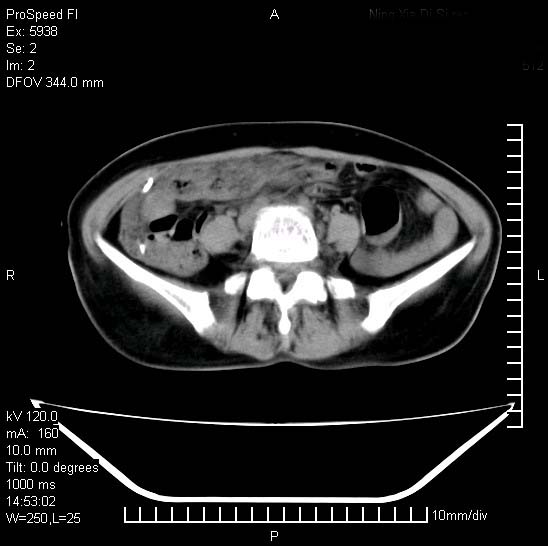

反复小腹疼痛,盆腔积液3年,无发热,曾抗痨一段时间。

右下腹肠管壁增厚,边缘有侵润改变及点状低密度影,内侧可见局限性肿块。考虑-----淋巴瘤或增生型肠结核----盆腔积液-----建议肠镜检查

考虑盆腔及右下腹感染性病变(结核可能)。

提示结核性腹膜炎合并盆腔积液。建议查ppd或tb抗体。

考虑右下腹及盆腔感染性病变(结核?)。